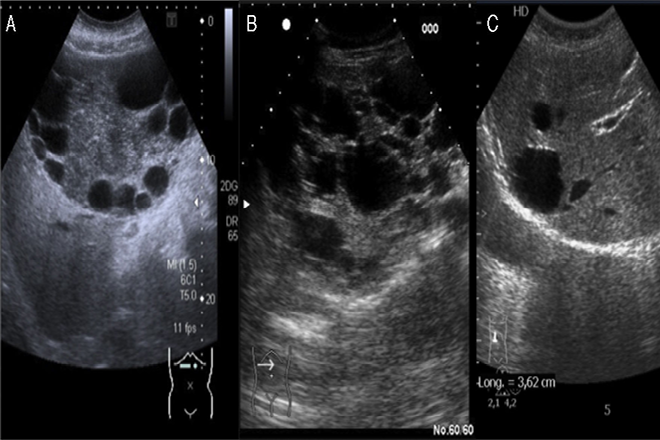

Aspecto eco endoscópico más característico de los tumores neuroendocrinos

El aspecto eco endoscópico más característico de los tumores neuroendocrinos es el de una tumoración redondeada, hipoecogénica, bastante homogénea, con límites precisos y refuerzo periférico producto de su abundante vascularización.

Sin embargo, no es infrecuente que el tumor sea hiperecogénico o isoecogénico en relación con el parénquima vecino o incluso quístico y, en algunos casos, sólo es visible con frecuencias de 12 MHz. Mientras que los Insulinomas son intrapancreáticos en el 99% de los casos (y pueden localizarse en todos los segmentos de la glándula), los gastrinomas sólo lo son en el 40 al 70% de los casos, se localizan preferentemente en la región cefálica del páncreas y en el 30% de los casos son múltiples.

En el caso de los tumores neuroendocrinos funcionantes, el diagnóstico de sospecha suele asentarse en la clínica del paciente y la existencia de valores hormonales elevados en sangre. Sin embargo, la localización del tumor es a menudo difícil, sobre todo en el caso de los gastrinomas e insulinomas, que suelen medir menos de 2 cm de diámetro.

La eficacia de la USE para el diagnóstico y localización de los tumores neuroendocrinos es del 90%, claramente superior a la ecografía, TC, arteriografía e incluso gammagrafía con octreótido.

En el caso de los gastrinomas, los resultados de la USE son ligeramente inferiores (70-80%) debido a que su localización puede ser extra pancreática. La USE-PAAF permite obtener un diagnóstico citológico de confirmación, aumentando la especificidad de la técnica.